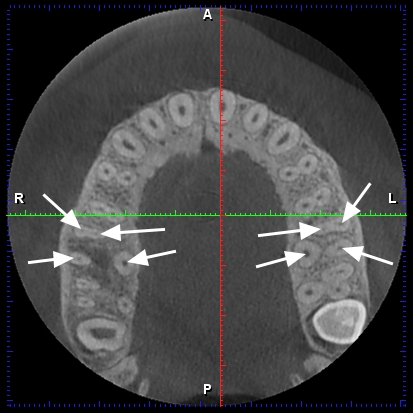

Endodontics: Topográfia gyökérkezelés és számuk